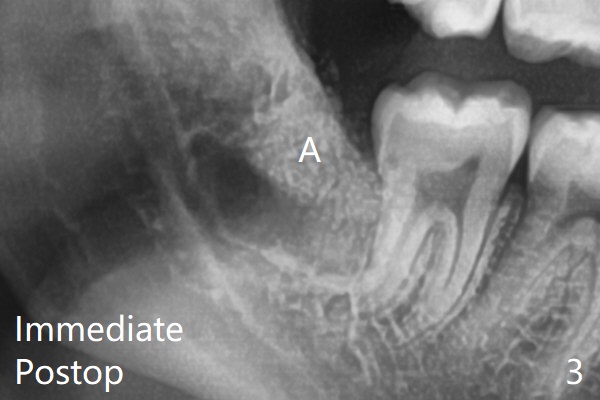

A 22-year-old man, asymptomatic, is going to have #1,16,17 and 32 extracted (Fig.1, fully bony impaction). For the large lower sockets (actually Buccal Impaction), collagen plug is placed in the inferior half, while Bone Cement (Bond Apatite from Augma (Fig.3 A)) and Osteogen plug (O) in the superior half at #32 and 17, respectively.